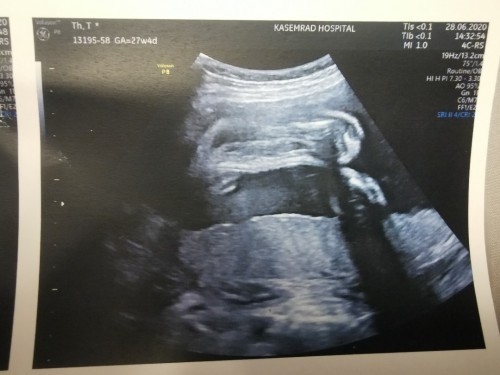

13 สัปดาห์ค่ะ

Post reply image